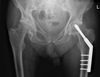

Dynamic hip screw (DHS)

Extracapsular NOF